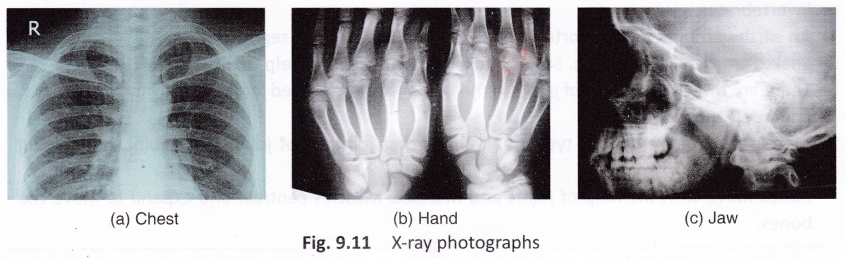

X-rays

Sometimes when we get hurt, doctors take an ‘X-ray’ photograph of the injured part to find out if there is any fracture in the bones. The pictures given in Figure 9.11 show X-ray images of different body parts. X rays were discovered by German physicist Wilhelm Conrad Roentgen in 1895. Roentgen discovered these rays accidentally, while working in his laboratory. In various experiments, he found that these rays were able to pass through tissues, but not through bones. Today, X-rays are commonly used in medicine (to diagnose fractures) and scientific research.